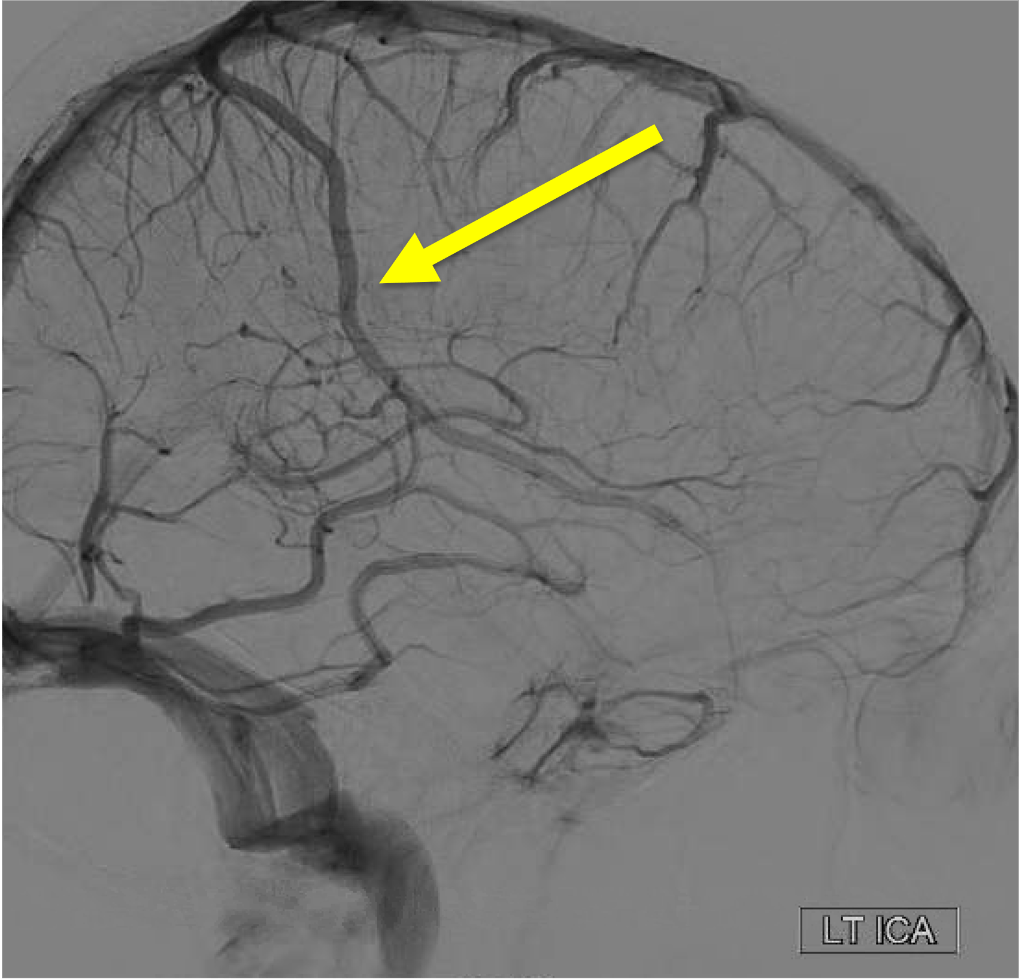

On the venous phase of this lateral L ICA injection, name the superficial vein: